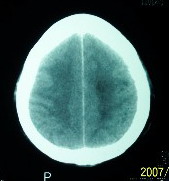

f    29岁   头闷  头晕1月余

肿瘤累及颅底前颅窝,部分层面见散在钙化,中心坏死。支持:脑膜瘤!

镰旁高密度灶,中间低密度坏死区,周围水肿较轻,支持脑膜瘤诊断,建议结合增强扫描。

右额叶底部巨大等低混杂密度肿块,边界清楚,周围水肿轻度,明显占位效应。蝶鞍扩大,部分骨质破坏。

考虑脑膜瘤,建议增强扫描进一步检查。